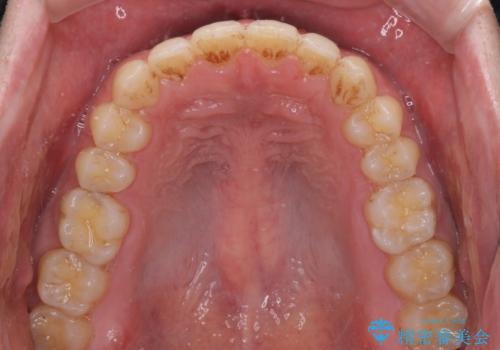

すきっ歯の改善 インビザライン矯正治療

インビザラインにより、上下の歯列を側方に拡大しつつ、前歯の隙間を閉じていくこととしました。

1日22時間の装着時間をしっかりと守ってくださったので、隙間がきれいに閉じ、口元の突出感も改善することができました。